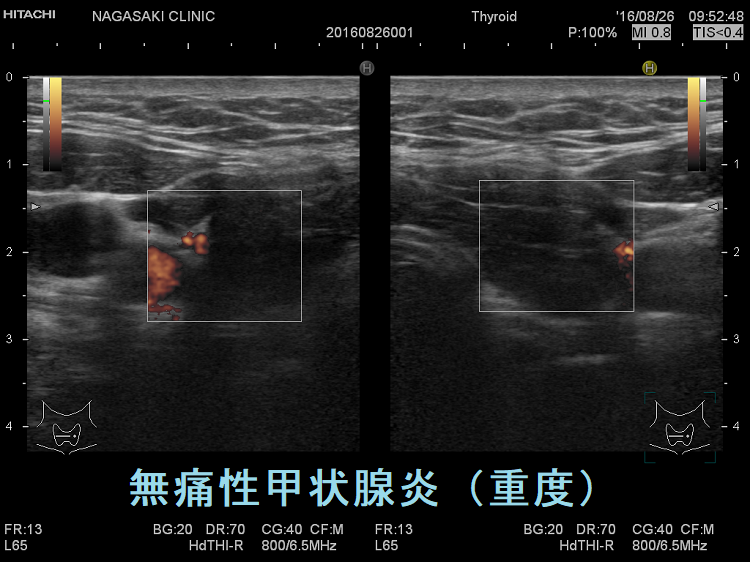

vascular index(血流指数)が増加した無痛性甲状腺炎

vascular index(血流指数)が増加した急性期の無痛性甲状腺炎の下甲状腺動脈の収縮期最大血流速度(ITA-PSV);ITA-PSVは低下しています。